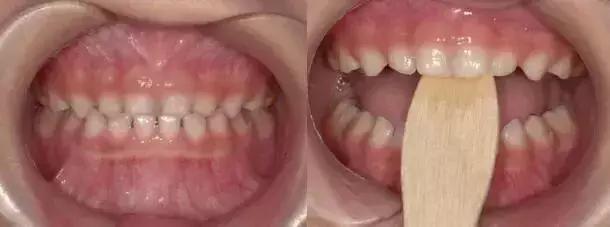

02、咬撬法

没得错,就是喊你咬棍棍儿!选择压舌板或牙刷柄,每天咬撬木板三次,每次大约2分钟(约20下),每两周复诊,1-3个月就阔以有效纠正“地包天”。